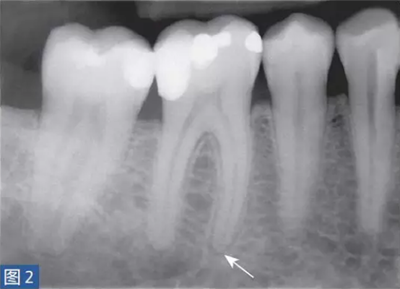

從牙髓炎過(guò)渡到根尖周炎(圖2 和3)的發(fā)生速度非???,牙齒表現(xiàn)可能從正常到對(duì)冷、熱和電刺激的反應(yīng)越來(lái)越強(qiáng)。當(dāng)牙髓已經(jīng)完全壞死時(shí),通常會(huì)顯示對(duì)牙髓電活力測(cè)試無(wú)反應(yīng)。牙齒可能會(huì)有伸長(zhǎng)感,用手指或口鏡柄施加壓力或者振動(dòng)牙齒會(huì)觸發(fā)非常嚴(yán)重的疼痛。放射學(xué)檢查可能存在透射區(qū)及根周膜間隙增寬,通常硬骨板和牙周韌帶沒有病理學(xué)特征。

圖2: 46 牙齒SAP。術(shù)前X 線片,該牙齒在其他醫(yī)生處已行齲齒治療?;颊咴V牙齒有明顯的咬合痛以及強(qiáng)烈的冷熱刺激敏感癥狀。放射學(xué)檢查,近中根根周膜間隙略增寬。